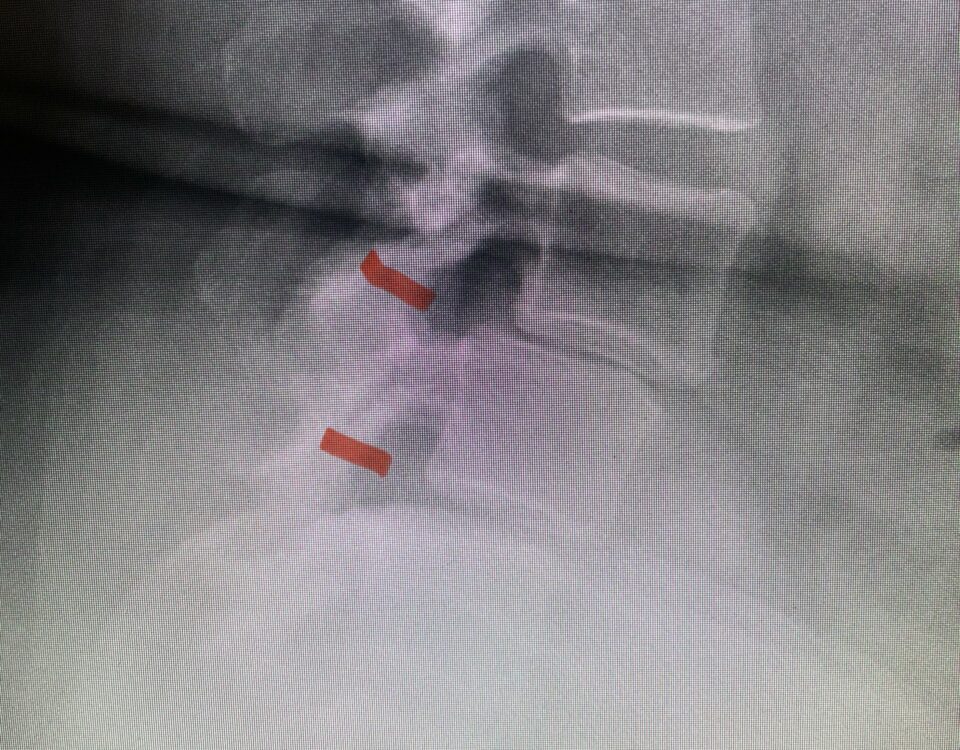

The spinal synovial cyst is one of the most interesting expressions of spinal instability. They emanate from the synovial lining of a degenerated facet joint that […]